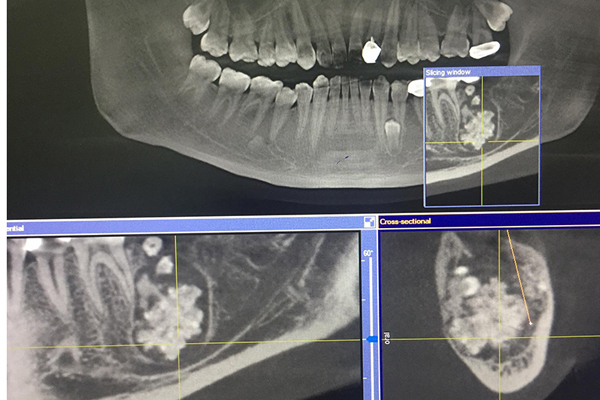

Tuy nhiên, kết quả chụp răng toàn cảnh của bệnh nhân cho thấy có khối u răng ở gần vị trí khuyết. Bác sĩ chỉ định phẫu thuật loại bỏ khối u.

Hình ảnh khối u trên phim chụp X-quang

Bệnh u răng rất khó để phát hiện do khối u không gây đau nhức, chỉ qua phim chụp X-quang răng toàn cảnh (Panorama toàn hàm) mới có thể nhìn thấy. Một số trường hợp u nang bị bội nhiễm, có đường rò, xương bị phá hủy sẽ có triệu chứng rõ ràng.